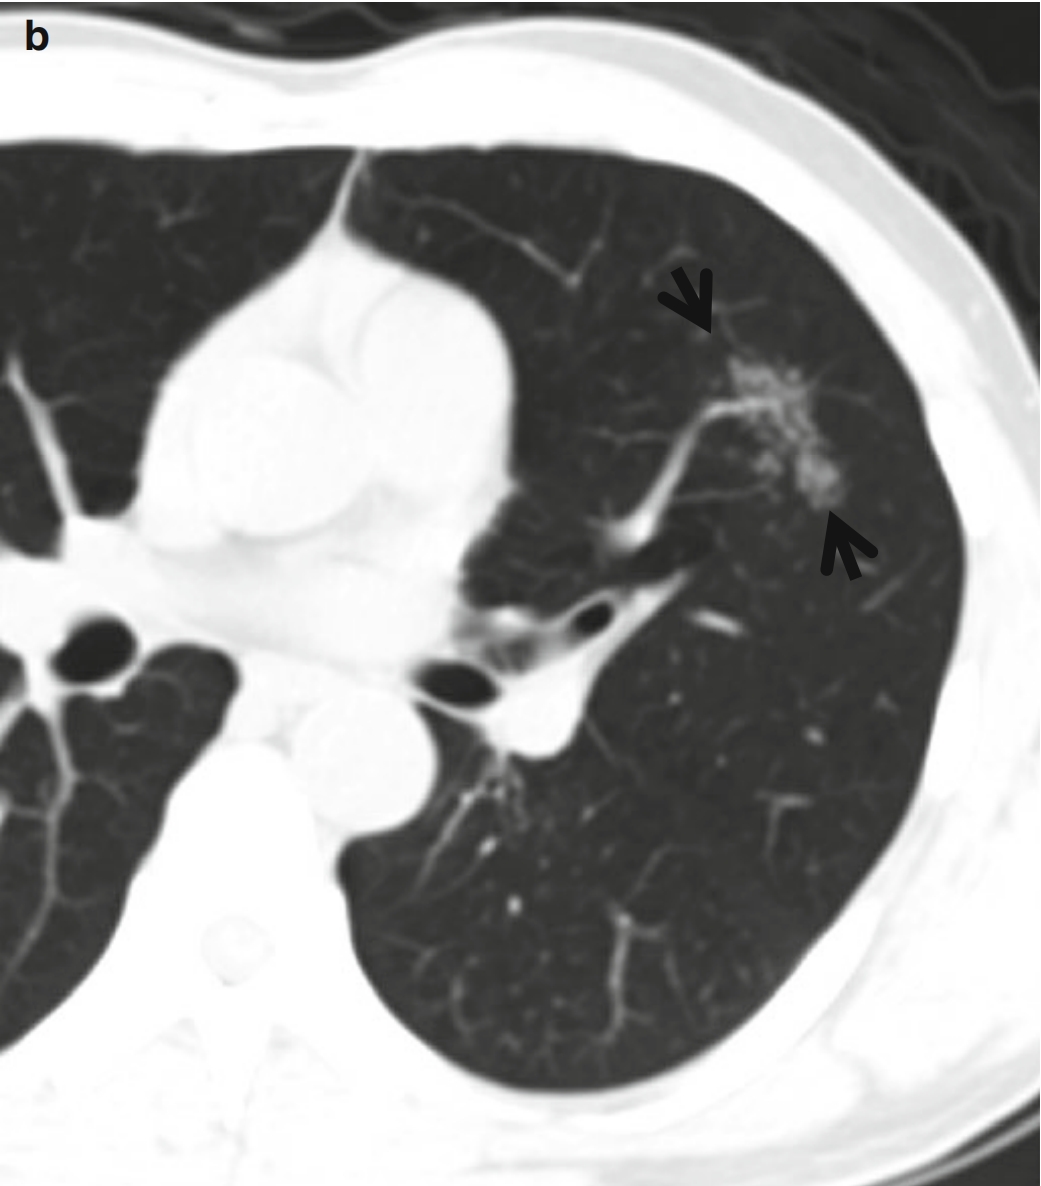

图2 CT星系征。

患者男性,44 岁,活动性肺结核。

(a.b)连续CT扫描(层厚=5.0 mm,低剂量模式)于右中间段支气管水平,可见左肺上叶上舌段CT星系征(箭头所示)。在层厚相对较厚的CT图像上。需要注意的是,不能把星系征看成磨玻璃密度影而诊断为浸润性肺腺癌。